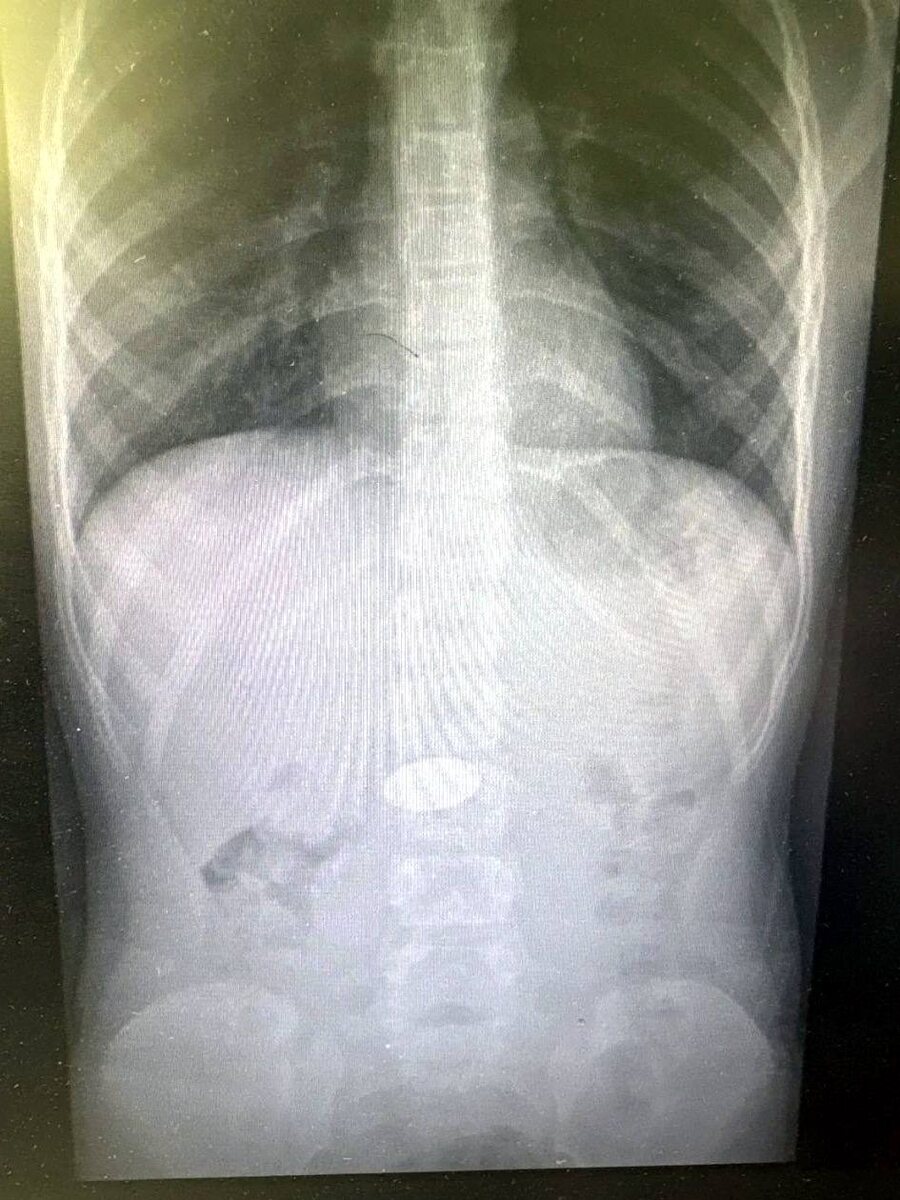

Врачи спасли малыша, проглотившего 5-рублёвую монету! 🫣

🏥👨‍⚕️ В Волгограде в больницу №7 поступил маленький ребёнок. Врачи обнаружили в его желудке крупную 5-рублёвую монету, которую он проглотил из-за недосмотра родителей.

Благодаря профессионализму медиков монету быстро извлекли, и малыш вернулся домой.